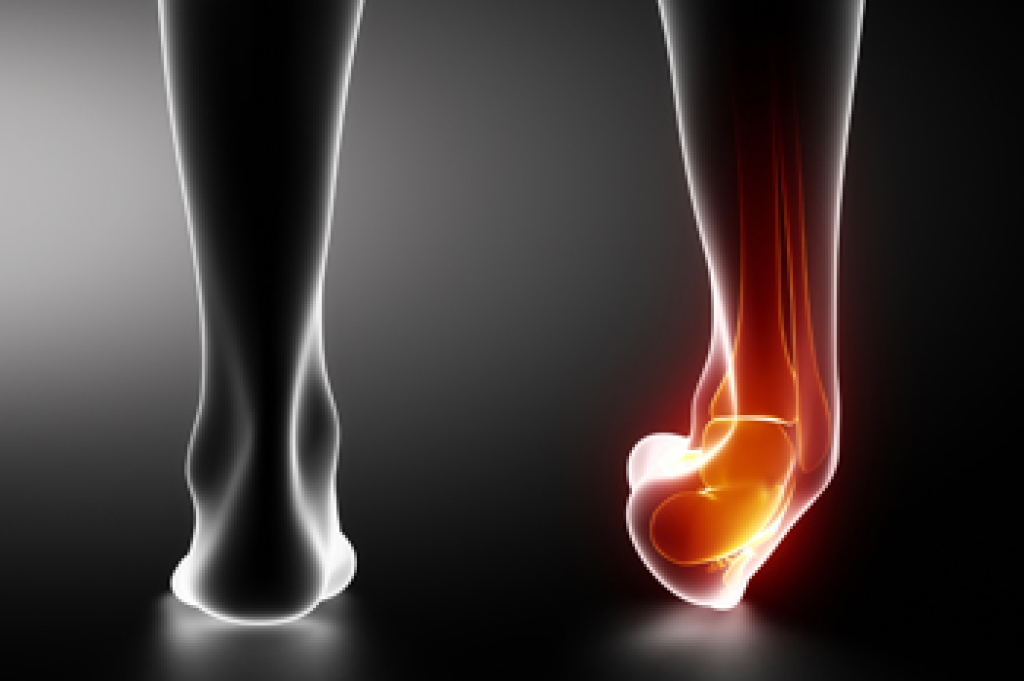

Pain in the big toe can stem from several foot conditions that affect the bones, joints, or soft tissues. A bunion, for example, develops when the big toe angles toward the second toe, leading to swelling, irritation, and a bony bump at the joint. Ingrown toenails are another common cause of big toe pain, where the nail grows into the skin, producing tenderness and inflammation. Turf toe, which is a sprain of the big toe joint, often results from sports or other activities that put stress on the forefoot. Arthritis, in the metatarsophalangeal, or MTP, joint may also lead to stiffness and chronic big toe pain. Other sources include sesamoiditis, which irritates the small bones under the big toe, gout caused by uric acid buildup, and fractures or sprains from direct injury. If you have sharp pain in the big toe, it is suggested that you make an appointment with a podiatrist for an exam, diagnosis, and treatment.